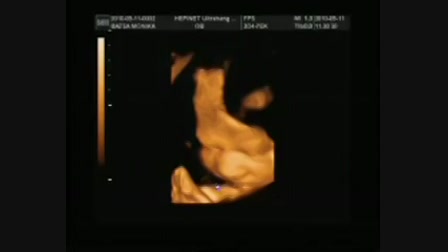

30. week tags (1)

00:17:43